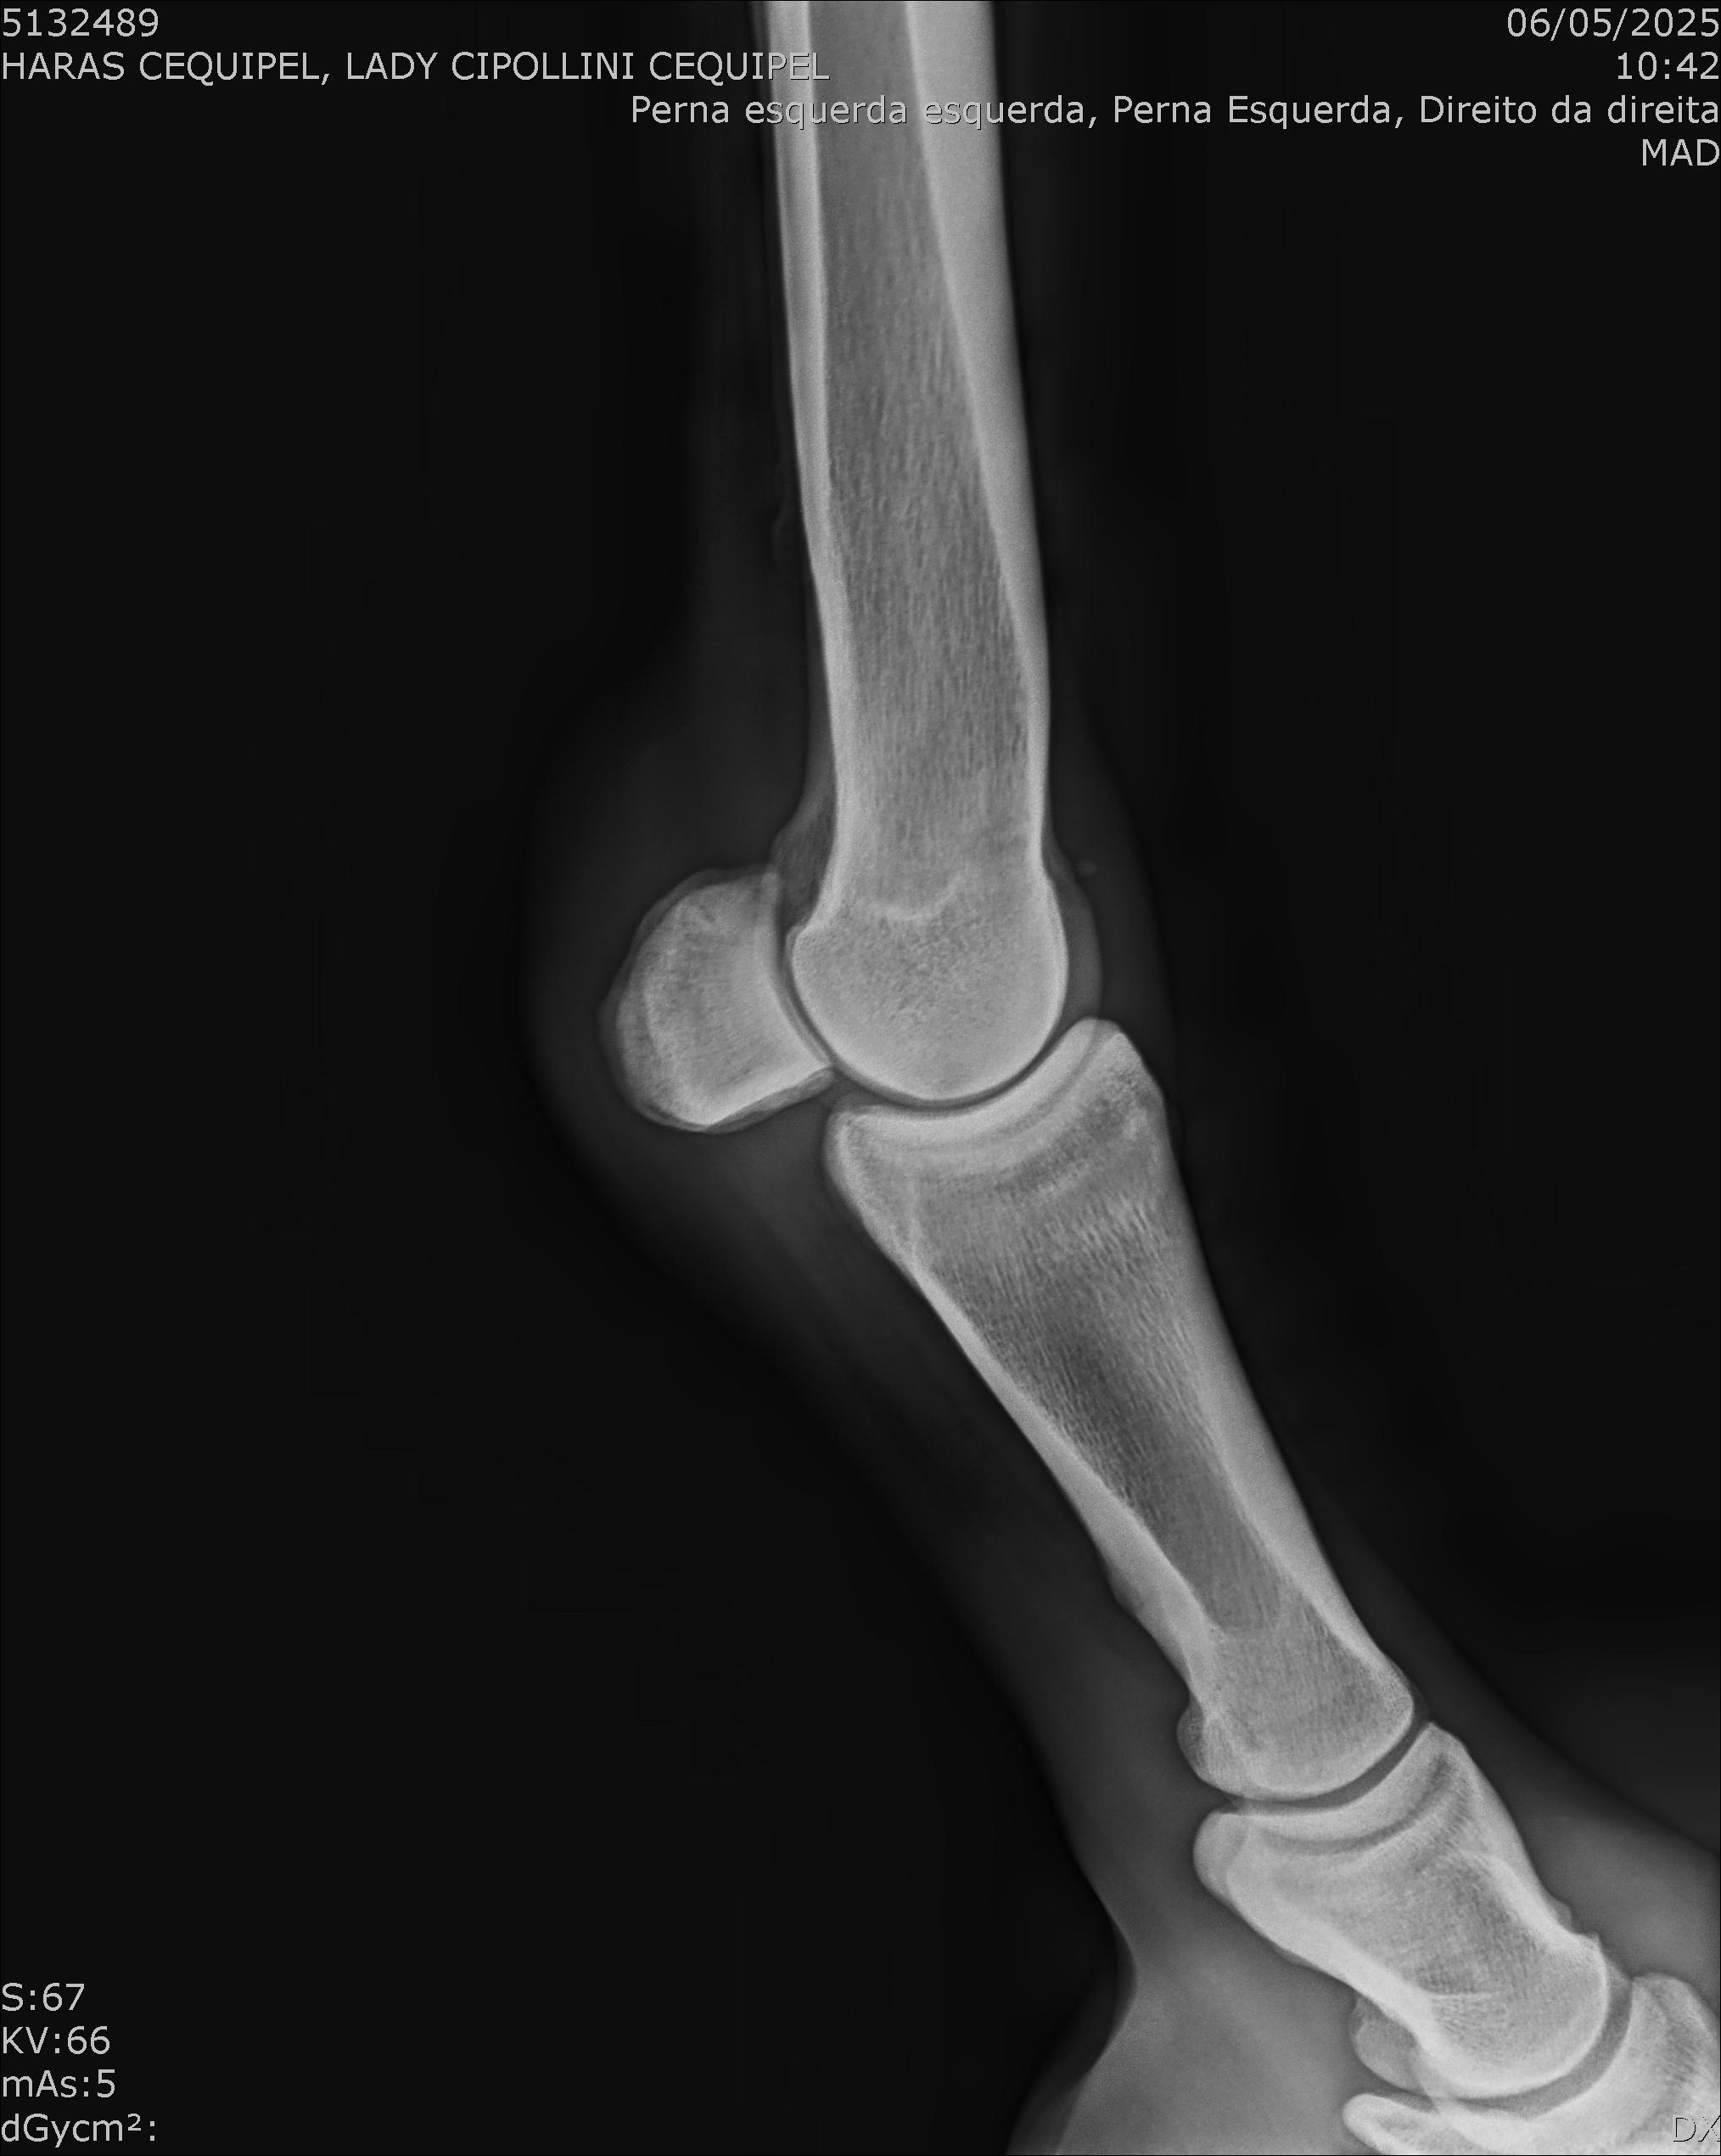

:: RAIOS-X DO LOTE